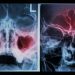

You should have a CT scan of your head to determine the cause of your condition. The CT scan is much more detailed than x-rays.

The CT scan can show the extent of any sinus problem. This can help your doctor decide if you need surgery to clear your sinuses or not.